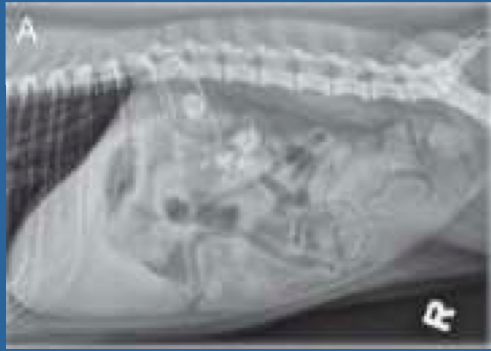

Best way to Diagnose Nephrolithiasis

Survey Radiographs

*Most Nephroliths are Radioopaque- Plain Radiographs are normally Diagnostic

Abdominal Radiographs